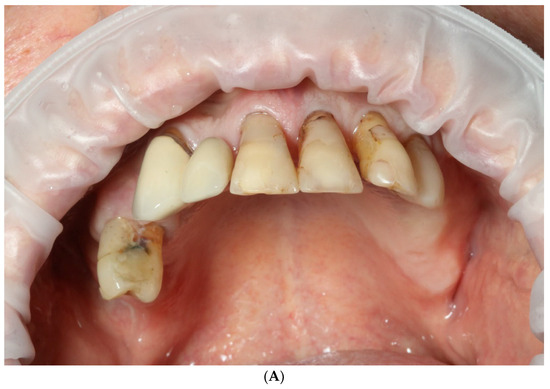

2.1. Patient Information and Clinical Findings

- Intraoral scan and CBCT;

- Meshmixer design of removable dentures;

- Three-dimensional manufacturing of removable dentures;

- Extraction of remaining teeth, immediate temporary implant placement, and removable denture delivery.